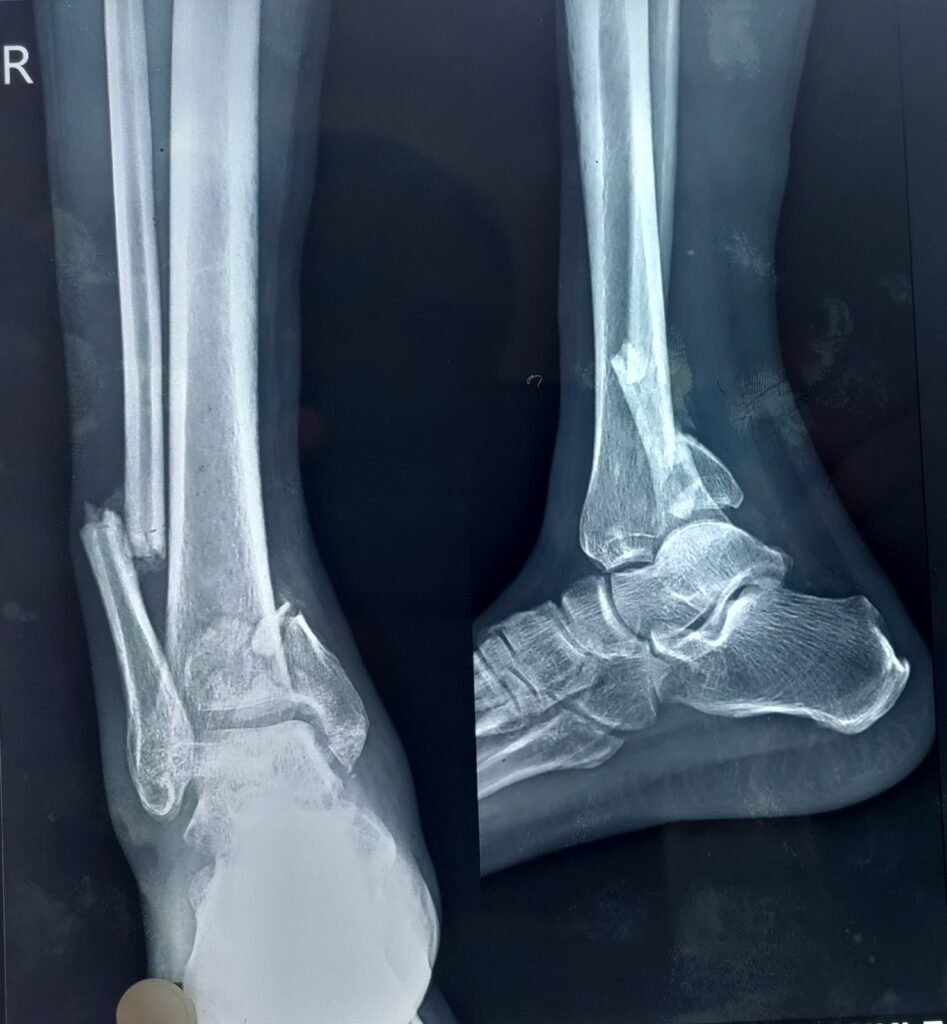

Minimal invasive calcaneum fracture surgery                                </p>

Minimal invasive calcaneum fracture surgery

Minimal invasive calcaneum surgery repairs heel fractures with small cuts, less pain, and quicker recovery.